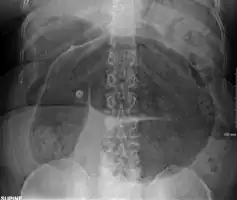

An x-ray of a person with a small bowel volvulus.

Plain X ray of a cecal volvulus -